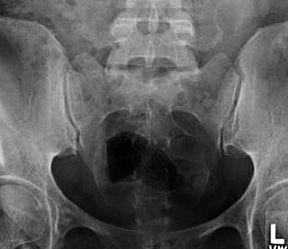

The lateral view of the sacrum/coccyx is performed with the patient in the standing / lateral position and the central ray directed vertical (perpendicular) to the sacrum. The purpose of the lateral view is to demonstrate the fifth lumbar vertebra, entire sacrum, and coccyx free of superimposition by fecal material and gas, and without the urinary bladder and rectum obstructing viewing. Notwithstanding, proper positioning of the sacrum / coccyx in a true lateral is an essential diagnostic criterion. Patient stands in lateral position with feet shoulder-width apart. Have patient cross arms at shoulder level. Locate the iliac crest and symphysis pubis. The horizontal CR is midway between iliac crest and symphysis pubis. The vertical CR is 2-3 inches posterior to the mid-coronal plane. Center film to horizontal CR. Collimation is slightly less than film size. (Figure 4)

Figure 5: Lateral view of the sacrum and coccyx.

When properly aligned, the apophyseal joints of L5/S1 are superimposed, the greater sciatic notches are superimposed, the sacral canal is opened and the median sacral crest is in profile. On the lateral sacrum / coccyx, structures demonstrated include the entire fifth lumbar vertebra, entire sacrum / coccyx, and proper visualization of an opened sacral canal. The coccyx should not be overexposed, showing good recorded detail. (Figure 5) It may be necessary to use a high grid ratio and contact lead along the collimated edge of the field to reduce scatter radiation reaching the image receptor.